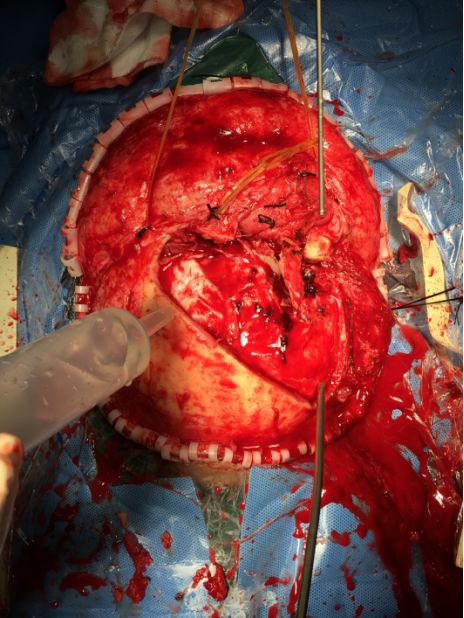

手术采用冠状切口,右侧额骨颧突部关键孔钻孔一个,左侧眉弓上方钻孔一个,离骨折边缘2-3厘米处铣刀铣成骨瓣,取下碎骨片,右侧眼眶大骨片未取下。硬膜多处裂开,清除硬膜外及少量硬膜下出血,清除少量挫裂伤脑组织,脑组织张力不高,缝合硬膜。左侧额窦予以骨蜡封闭,清除额底鼻骨碎骨片后,与鼻窦相通,复位右侧眶壁骨折。取颞肌修补覆盖颅底,封闭颅内与鼻腔眼眶之交通,再游离额部骨膜,反折覆盖颅底并固定。骨瓣及游离较大块碎骨片双氧水浸泡,依据形状复位碎骨片,缝线及胶水固定,复位骨瓣并钛钉固定。

![]()

带蒂骨膜反折覆盖颅底,加固修补